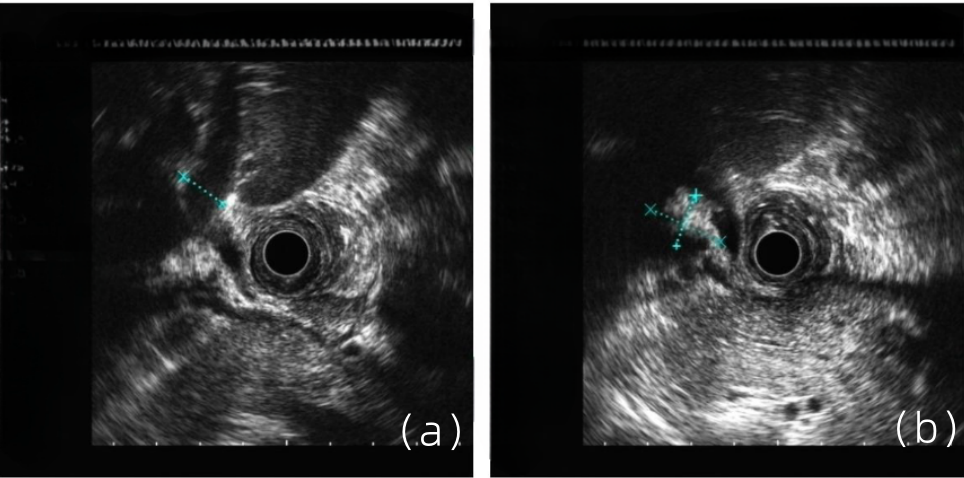

病史摘要:患者为 38 岁男性,因“发现乙肝 1 月余,腹痛 1 天”入院。1 月前诊断为“失代偿期肝硬化(脾大、腹水、门脉高压、食管静脉曲张)乙肝”,经抗 HBV、保肝治疗后症状缓解。入院前 1 天突发剑突下疼痛,进食后稍缓解,入院当日腹痛加重,伴恶心、呕吐。有吸烟及不规律饮酒史,现已戒酒,母亲因“肝硬化”去世,无慢性基础疾病、手术史、过敏史及有毒有害物质接触史。

乙肝肝硬化患者合并肝门部胆管狭窄致梗阻性黄疸罕见病因1例